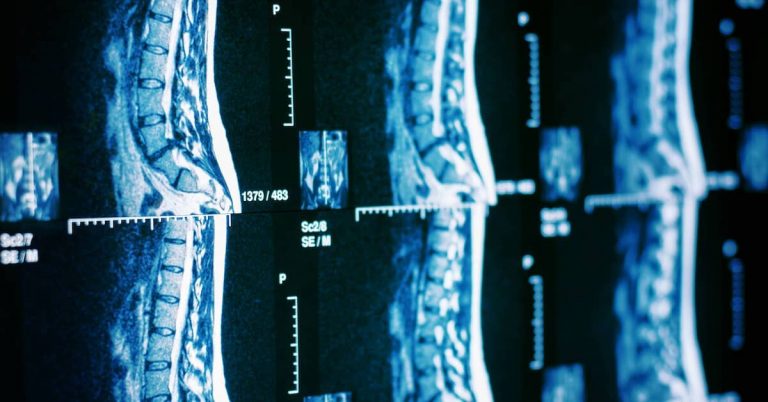

24-year-old Californian Colin Bossy shares his inspiring story of determination after a tragic surfing accident left him paralyzed from the chest down. Last year, while swimming with friends, Collin dived into shallow, murky water, resulting in a traumatic spine injury (SCI). Undeterred, Colin worked with a team of volunteers to build a custom-made surfboard controlled by his forearms. Against all odds, Colin successfully rode the waves for the first time since his accident. Despite the initial coldness, Colin felt a sense of being at home again and expressed gratitude for the experience. His perseverance serves as an inspiration to others.